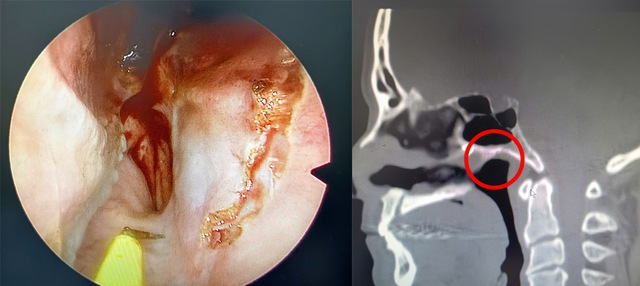

Dị vật nằm sâu trong mũi của bệnh nhân hơn 40 năm.

Tại lần thăm khám này, các bác sĩ đã chỉ định nội soi tai mũi họng và chụp cắt lớp vi tính xoang để đánh giá toàn diện. Kết quả nội soi cho thấy tình trạng thủng vách ngăn mũi và niêm mạc đã có biến đổi mạn tính. Đặc biệt, hình ảnh chụp cắt lớp vi tính đóng vai trò then chốt khi phát hiện rõ một dị vật cản quang. Vị trí của dị vật nằm rất sâu và hiểm hóc: thuộc phần sau trên của vách ngăn mũi phải, cách cửa mũi trước khoảng 7 cm và nằm sát mặt trước xoang bướm.

Các bác sĩ thành công lấy được dị vật từ trong mũi bệnh nhân.

Chính nhờ kết quả chẩn đoán hình ảnh chính xác này, các bác sĩ đã xác định được thủ phạm gây viêm mạn tính và những cơn đau đầu dai dẳng của người bệnh suốt nhiều năm qua.